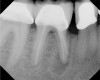

Fig 13. Tooth was asymptomatic at 1-year follow-up. Courtesy of Dr. Guillaume Jouanny.

Figure 13

Fig 14. Contralateral tooth at 1-year follow-up. Courtesy of Dr. Guillaume Jouanny.

Figure 14

In this case, the tooth tested vital but showed clinical signs of irreversible pulpitis. Treatment with a full pulpotomy was chosen to improve the chances the remaining pulp would survive and remain healthy. The preoperative radiograph in Figure 11 shows extensive caries in the tooth and a slightly widened apical periodontal ligament. A full pulpotomy was performed using the BC putty (Figure 12). After the putty set, a coronal restoration was placed, and an immediate postoperative radiograph was taken and viewed. At the 1-year follow-up, the tooth was asymptomatic, and the radiograph showed continued root development (Figure 13), a healthy apical periodontium, and, importantly, no calcifications in the remaining pulp (as is often seen with a calcium hydroxide therapy). A radiograph taken of the contra-lateral tooth showed similar root development (Figure 14).